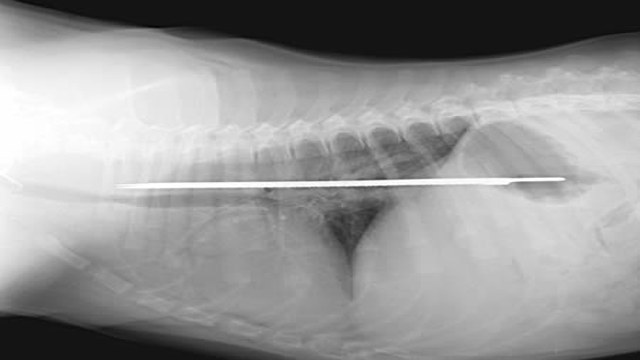

9. Chú cún thích nuốt dao

Con dao dài gần 33cm này không hiểu bằng cách nào lại nằm gọn lỏn trong dạ dày của một chú chó dòng Saint Bernard ở Florida tới 4 ngày trước khi chủ nhân phát hiện ra và đem chú đi phẫu thuật. Chú chó, dĩ nhiên, sau đó tiếp tục sống một cách khỏe mạnh và có vẻ như chưa nuốt thêm con dao nào khác.